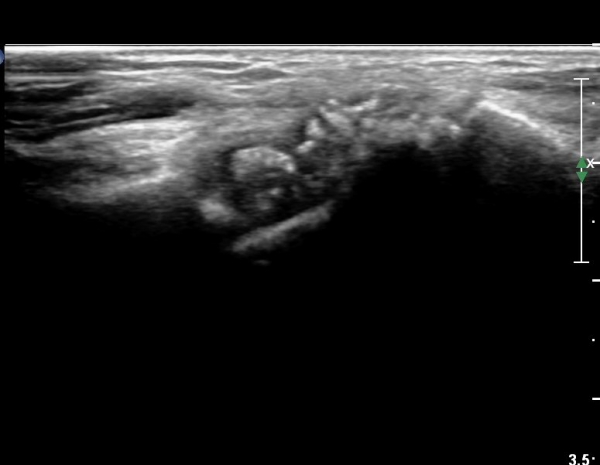

ÈûÁÙ ¹× Á¤Á߽ŰæÀÇ Ç¥ÃþÀ¸·Î ÀüÀ§°¡ °üÂûµÈ´Ù, (»çÁø 1 ), ÆÄ¿öµµÇ÷¯°Ë»ç¿¡¼ Ç÷·ùÁõ°¡°¡ °üÂûµÊ´Ù(»çÁø 2)..